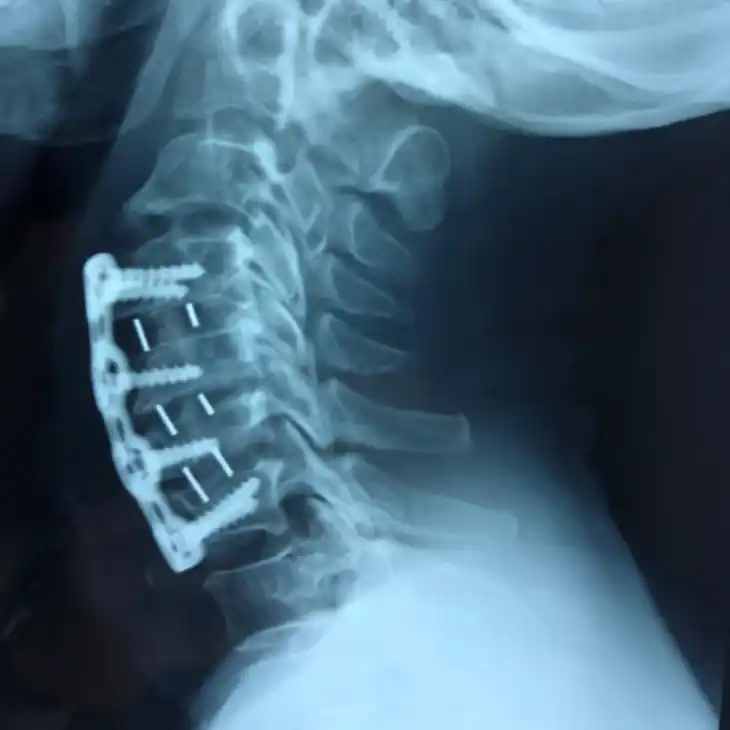

Durante o procedimento, utilizamos enxertos ósseos e implantes metálicos (parafusos, hastes e placas) para criar uma estrutura sólida e estável. Com o tempo, o osso cresce e se funde naturalmente, formando uma única estrutura óssea contínua.

Artrodese Cervical

Fusão das vértebras cervicais para tratar hérnia cervical, mielopatia, instabilidade e deformidades da região do pescoço.

• ACDF (Discectomia e Fusão Cervical Anterior)

• Corpectomia cervical

• Fusão cervical posterior

• Preservação da mobilidade